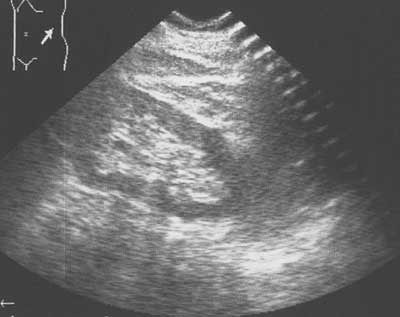

Рис. 4. Эхограмма левой почки. Жидкость из полости кисты эвакуирована. Четко определяются все сегменты почки.